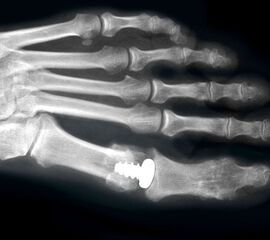

Die ersten Versuche mit der Prothetik am Großzehengrundgelenk wurden mit metallischen Hemi-Implantaten (Abb. 13, 14) vorgenommen. Eine Studie 47 mit größerem Kollektiv im Langzeitverlauf zeigte befriedigende Resultate, trotzdem hat sich die Technik bis heute nicht wirklich durchgesetzt. Der gleiche Autor verglich die Endoprothese mit der periartikulären Osteotomie und konnte keine wesentlichen Unterschiede feststellen 48. Eine neuere Studie vergleicht die Hemiarthroplastik mit der Arthrodese und der Resektionsarthroplastik und kann keine signifikanten Unterschiede feststellen 49. Metall–Polyäthylen-Paarungen zeigten eine hohe Lockerungsrate der Komponenten, weshalb sich diese Paarung ebenfalls nicht durchsetzte 505152. Am meisten Erfahrung besteht mit der Silikonprothese. Initial als Hemiprothese propagiert 46, wurde wegen mangelhaften Erfolgen 5354 die Totalprothese mit zwei Schäften eingeführt 55. Die Langzeitergebnisse sind widersprüchlich 55565758 so dass wegen der Verunsicherung dieses Model aktuell nicht regelmässig zum Einsatz kommt.